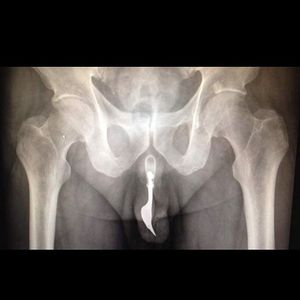

This happened as a result of a strange and unlucky sexual accident. He arrived to the hospital and presented with bleeding from the area. The fork was not visible but doctors were able to feel it from the outside and X-rays showed its position.You ask why? He told he had inserted the 10cm dining fork into his urethra almost 12 hours earlier in an attempt to achieve sexual gratification.The doctors removed the item without any surgical intervention, in order to minimise urothelial trauma and preserve erectile function.